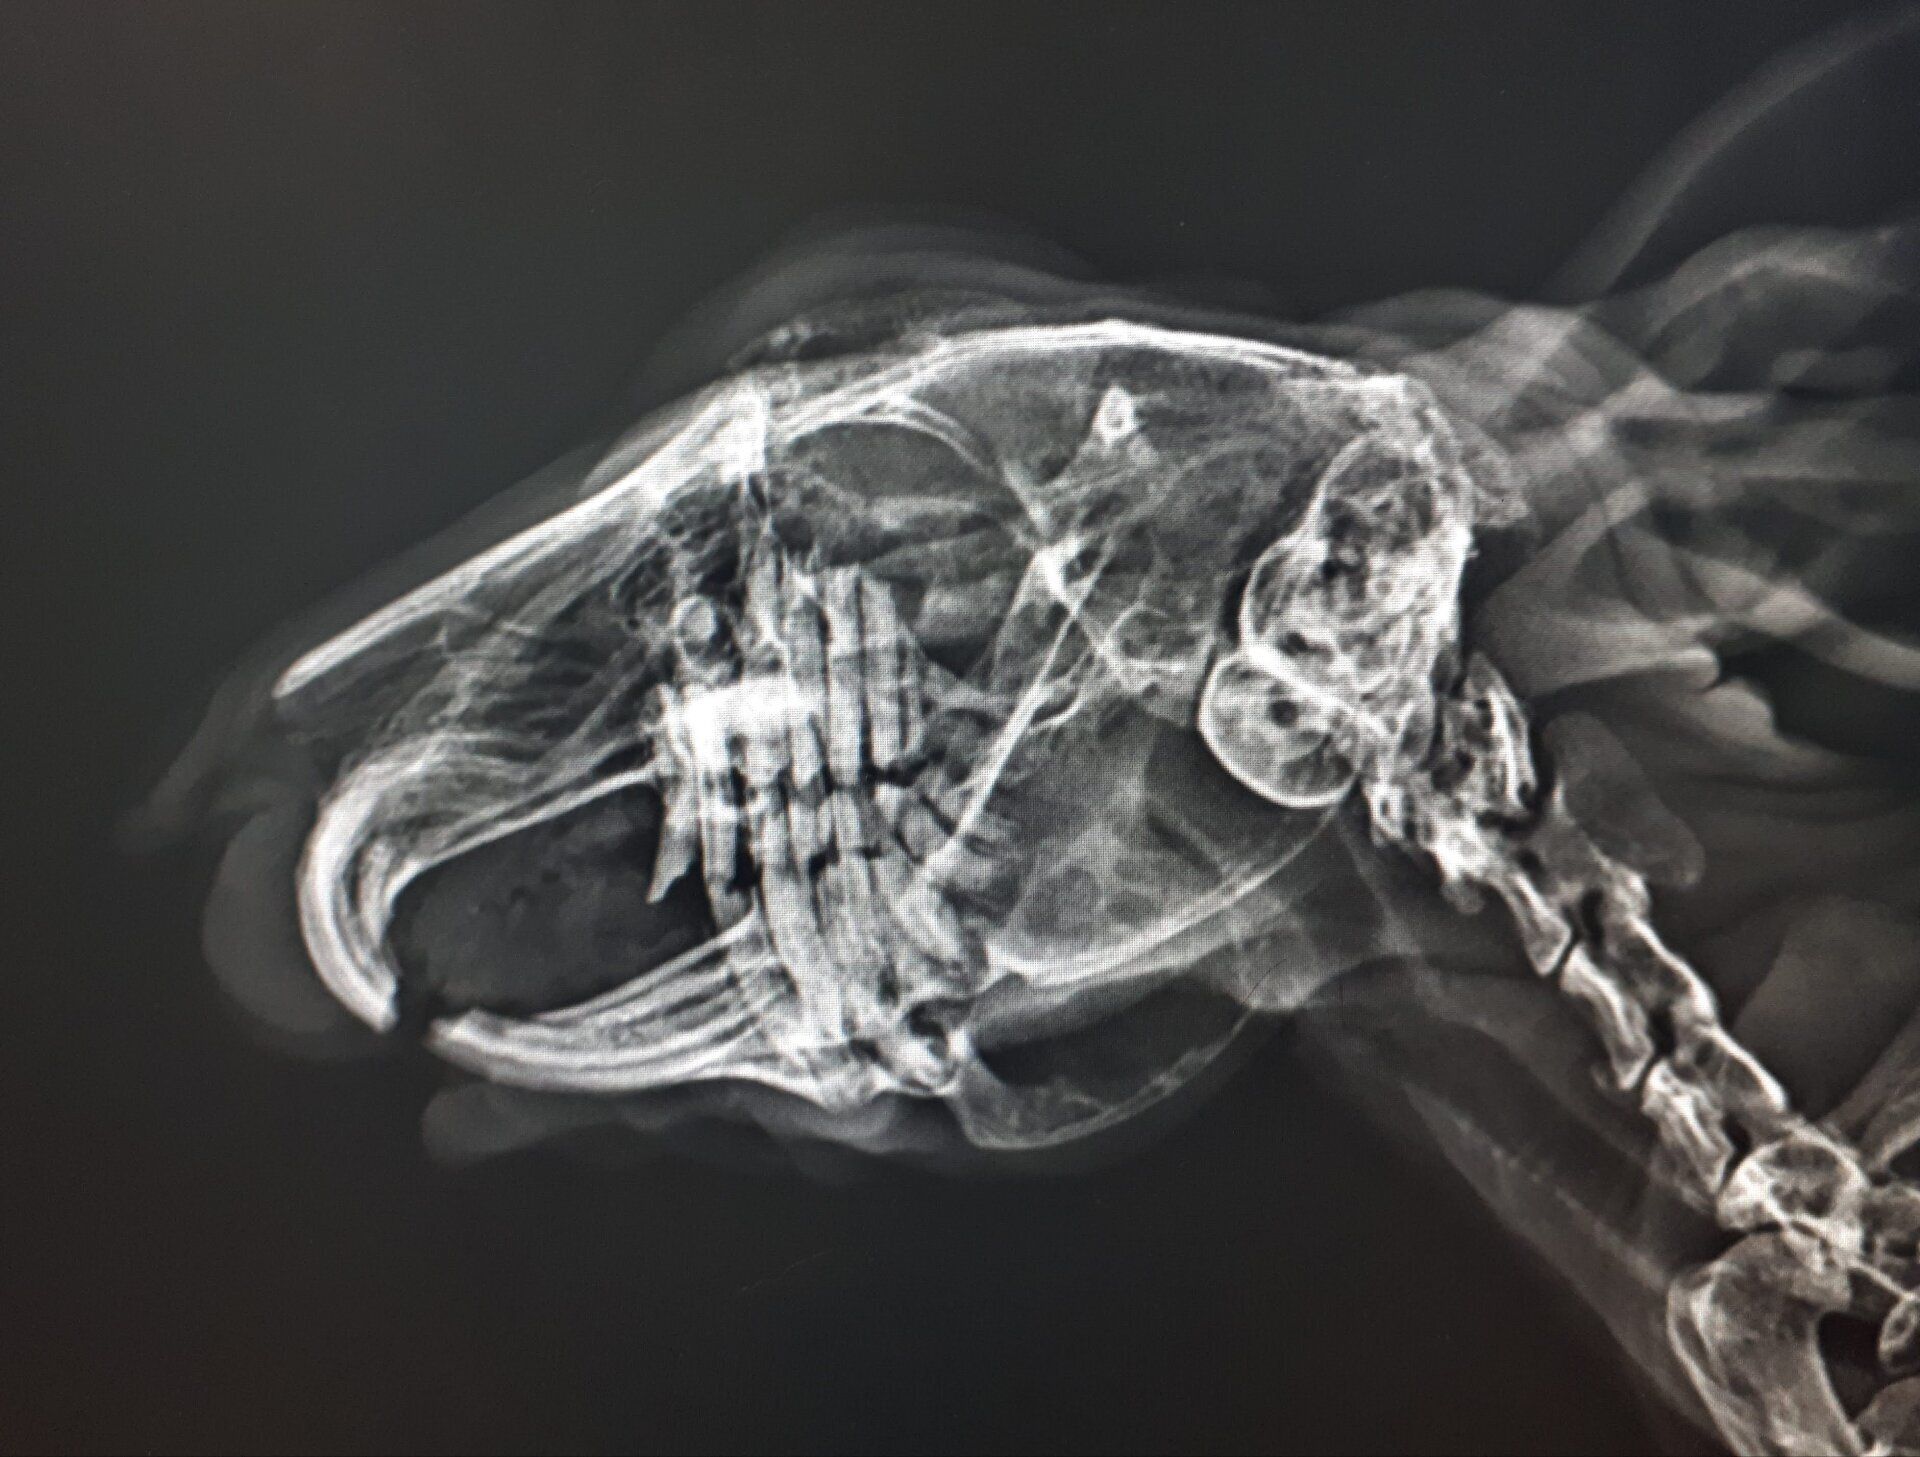

Diagnostica per immagini

Tra i servizi che l’Ospedale Veterinario Città di Conegliano fornisce, non mancano quelli di diagnostica per immagini:

ecografia, radiologia digitale, TC.

Gli specialisti Roberto De Pellegrin e Riccardo Pelizzon, in particolare, si occupano degli esami ecografici, ecocardiografici, tomografici per l'acquisizione di immagini del corpo del paziente attraverso l'esposizione a ultrasuoni o a raggi X.

Si tratta di esami non invasivi né dolorosi, che possono essere eseguiti molto rapidamente.